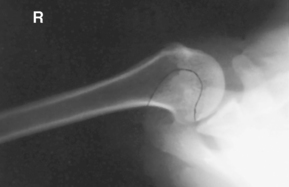

Tangential projection—intertubercular (bicipital) groove (Fisk modification) (S)

Tangential projection intertubercular groove critique